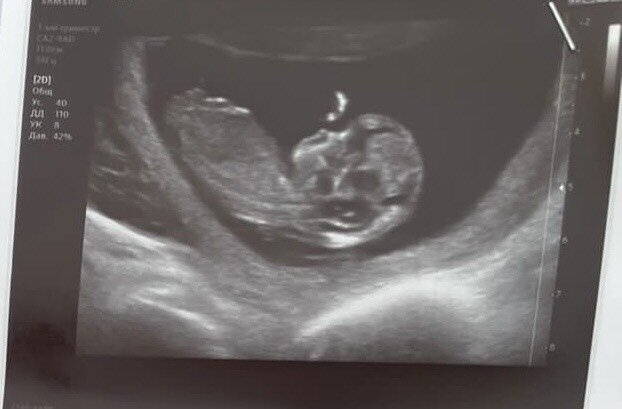

Так грустно, достану всех сегодня точно, пока не отойду, так ждала узи, (не пишите, что на 12 неделе ничего не видно), хотела гендер пати, так как муж потом уезжает, когда приедет, точно неизвестно( совсем расстроилась ? но, услышала сердечко, и сказали, что все хорошо (тьфу, тьфу), лежу, насмотреться не могу

Посмотрите на мое узи, что-то в нижней части похожее есть? ??